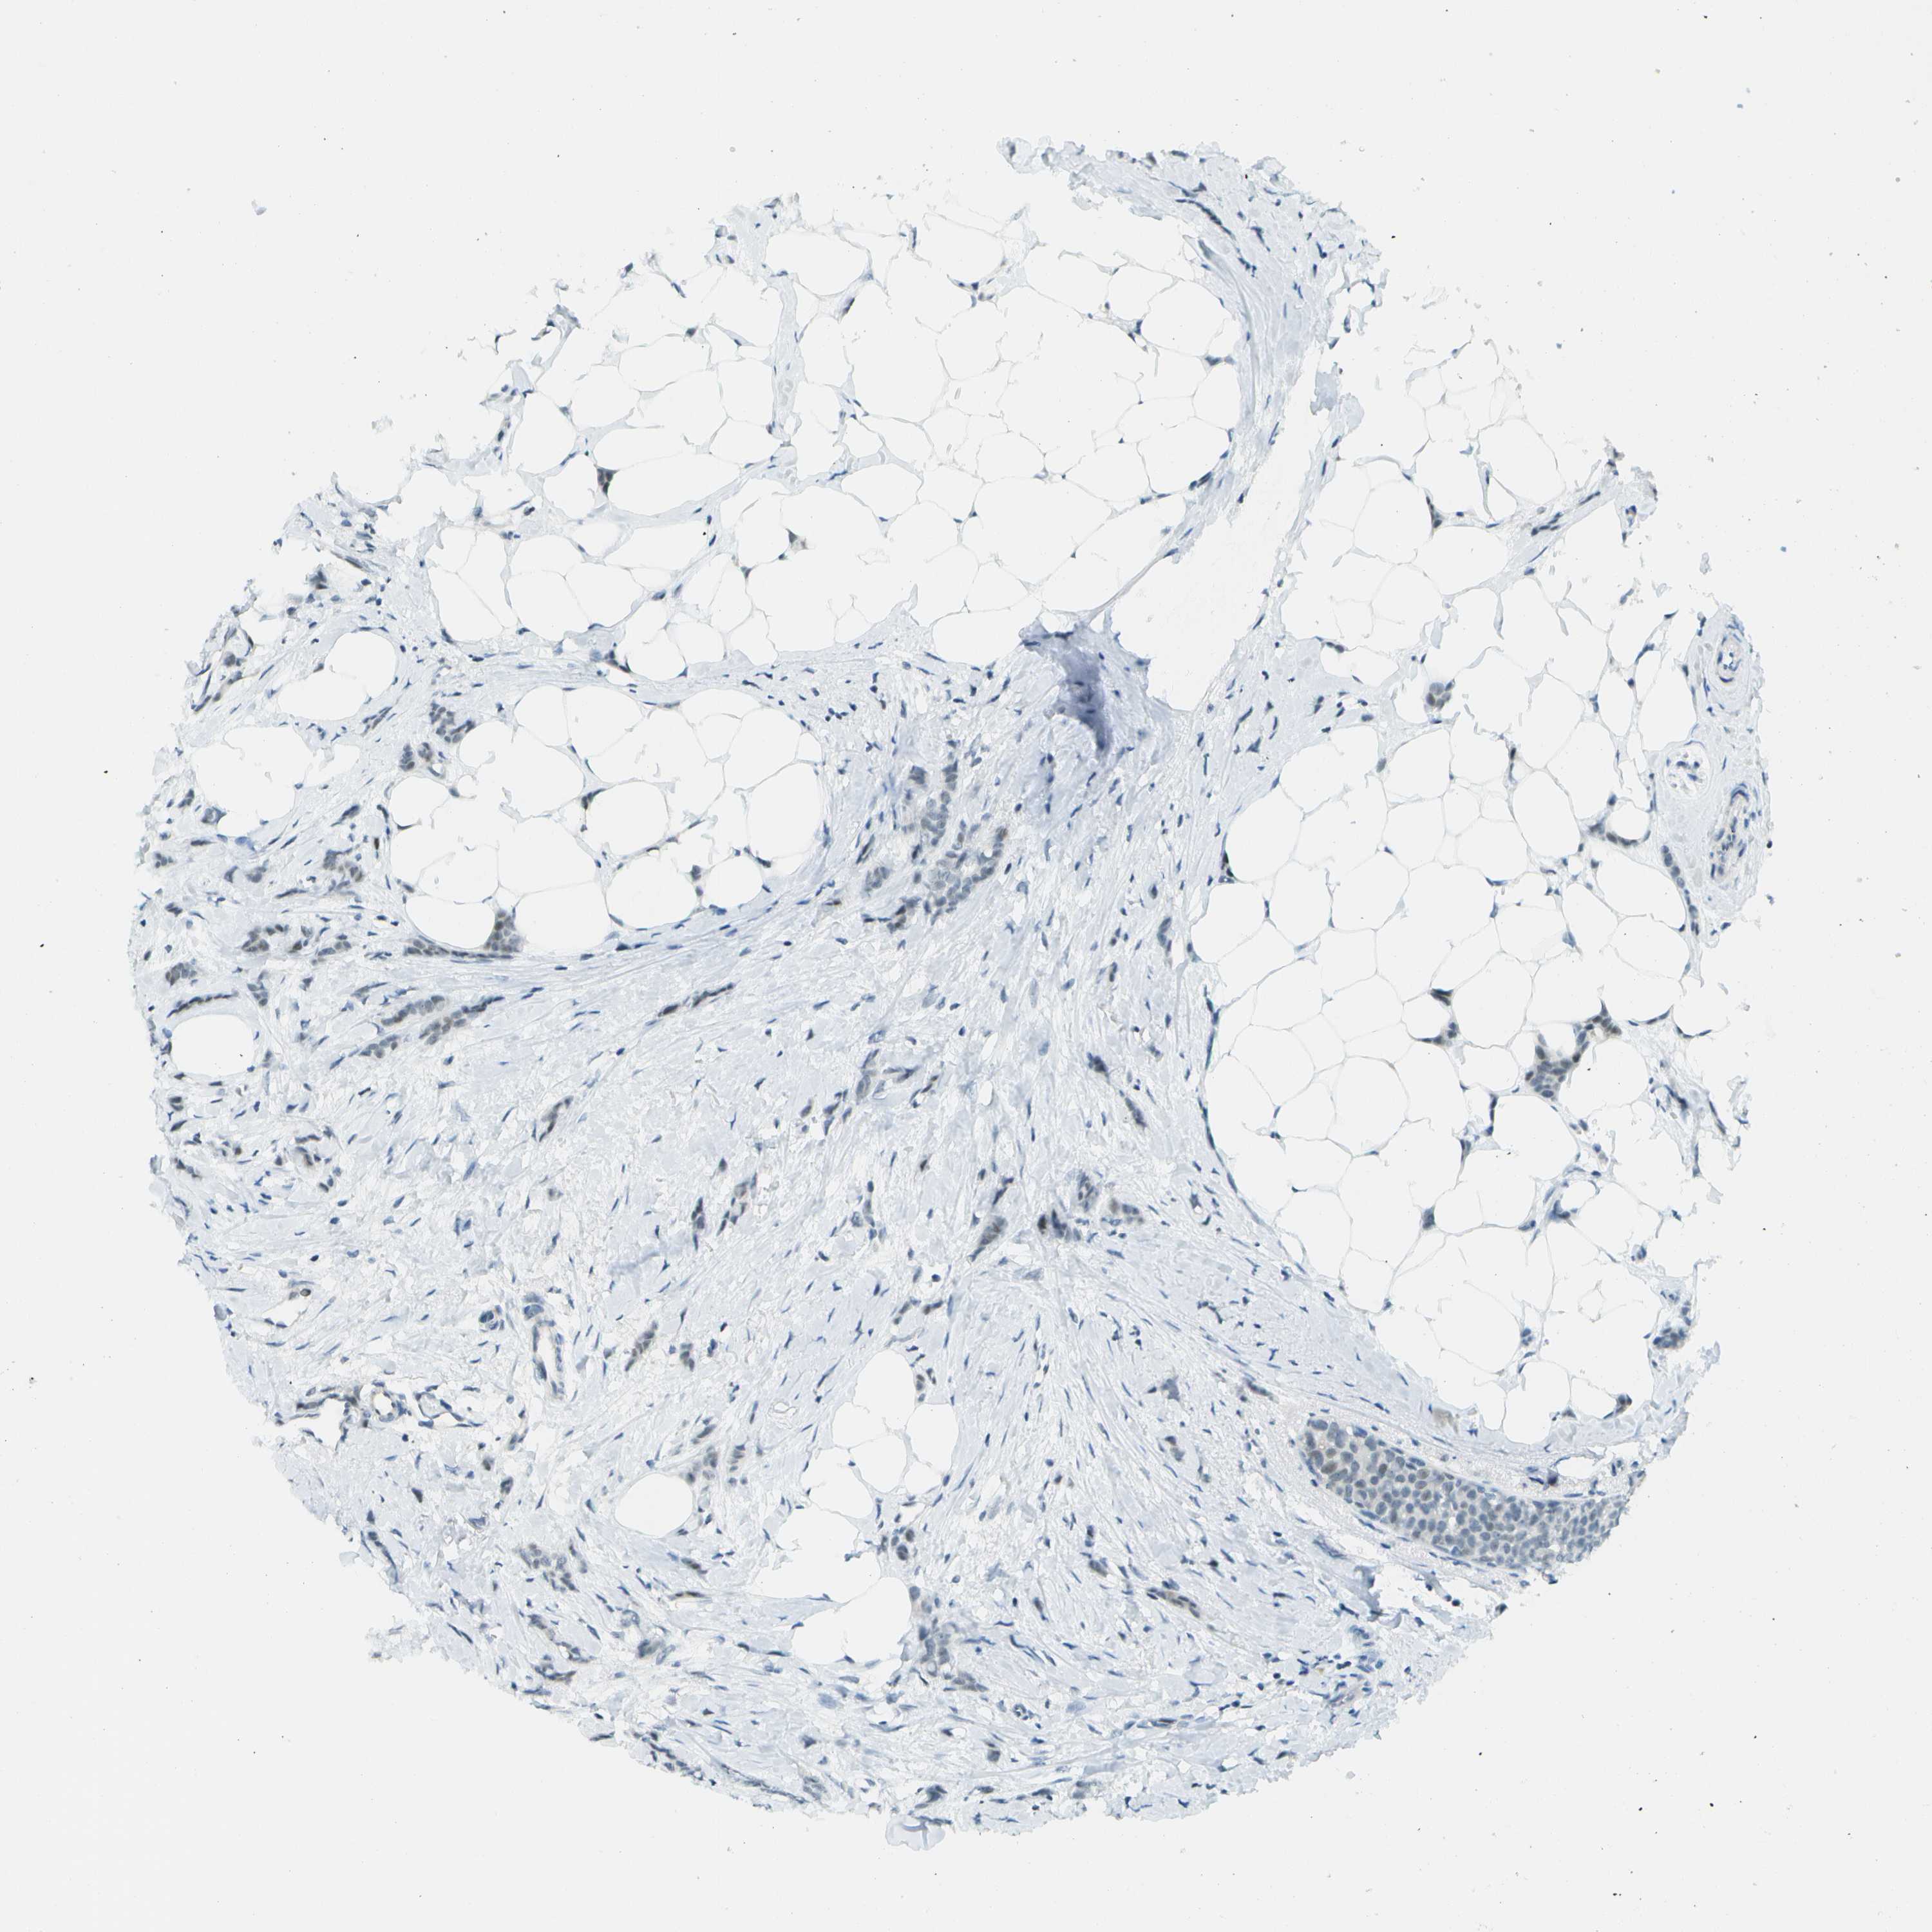

CANCER BREAST CANCER Show tissue menu

BRCA TCGA BRCA VALIDATION PROTEIN EXPRESSION